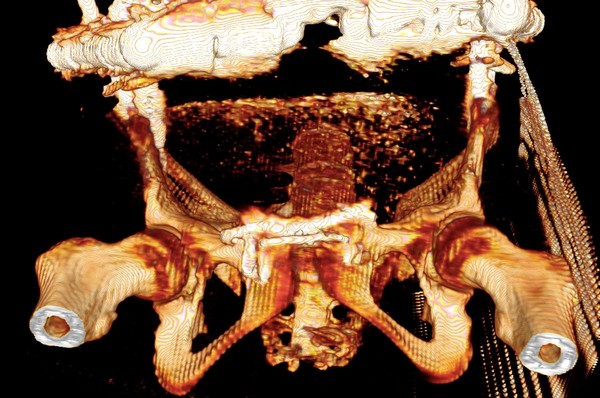

Девочка 14 лет. Кататравма (падение с высоты 4-5 этажа). Вертикально нестабильный перелом таза со смещением, разрывом лонного и левого подвздошно-крестцового сочленения, перелом крестца, открытый перелом костей голени. Ребёнок оперирован на 10-е сутки после травмы - выполнили максимально возможную репозицию на ортопедическом столе, синтез лонного сочленения реконструктивной пластиной (из имеющихся пластин - на 7 дыр - самая длинная, получилось только по 2 шурупа с каждой стороны, поэтому пришлось подстраховаться проволокой), АВФ. Задний комплекс не фиксировали ввиду отсутствия канюлированных (да и неканюлированных)шурупов должной длинны.В настоящий момент перед нами стоит вопросов:1. Обязательно ли фиксировать подвздошно-крестцовое сочленение, либо фиксации АВФ будет достаточно? Аппарат стоит достаточно стабильно, девочка при перемещениях в пределах постельного режима болевых ощущений не испытывает.2. Что делать с отломком крестца, который довольно значительно смещён кпереди? В настоящий момент никаких проблем с дефекацией у больной нет, хотя, глядя на КТ, создаётся впечатление, что отломок прямо-таки лежит на прямой кишке. Репонировать-фиксировать? Просто удалить? Вообще не трогать? Не создаст ли он в дальнейшем проблем во время родов?Хотелось бы знать мнение уважаемых коллег.Заранее спасибо.

Это не частый случай в детской практике. Вы очень хорошо сопоставили и фиксировали переднее полукольцо. Крестцово-подвздошное осталось в приличном смещении. Прекрасно - что нет неврологической клиники. Сейчас больная лежит. Поэтому всё хорошо. Учитывая соотношение крестец-подвздошная кость - кажется, что первые же проблемы возникнут при попытке поставить больного на ноги. Разорваны важнейшие стабилизирующие и воспринимающие нагрузку связки в системе позвоночник-крестец-таз. В таком положении фрагменов их адекватное восстановление и последующее функционирование , как мне кажется, не возможно. В возрасте 14 лет это взаимоотношение критично. Я имею в виду отсутствие репозиции. появление нестабильности, по-видимому, будет неизбежно. Это моё маленькое скромное мнение. Всё же надо было начинать сзади. Именно с репозиции. Фиксацию, ИМХО, можно было бы на безрыбье временно сделать и спицами (например-с резьбой) интраоперационно. В идеале - с навигатором, чтобы не задеть крестцовый канал, или с пальцем, контролирующим положение отломков над гребнем подвздоной кости и "навигирующим" проведение спицы. Сейчас Вам это сделать помешает LCP, жёстко фиксирующая переднее полукольцо и смещенное положение отломков. АВФ не "прижмёт" подвздошную кость к крестцу, и не выполнит репозицию. Возраст больной, мне кажется, не простит в дальнейшем погрешность в положении костей и, чем дальше, тем труднее будет исправлять . Это только мнение и ничего личного.Прямая кишка здесь в меньшей степени заинтересована - это вовсем не главное. Вероятные роды в насоящей тактике лечения совсем не играют решающей роли. Всё же - как неврология?